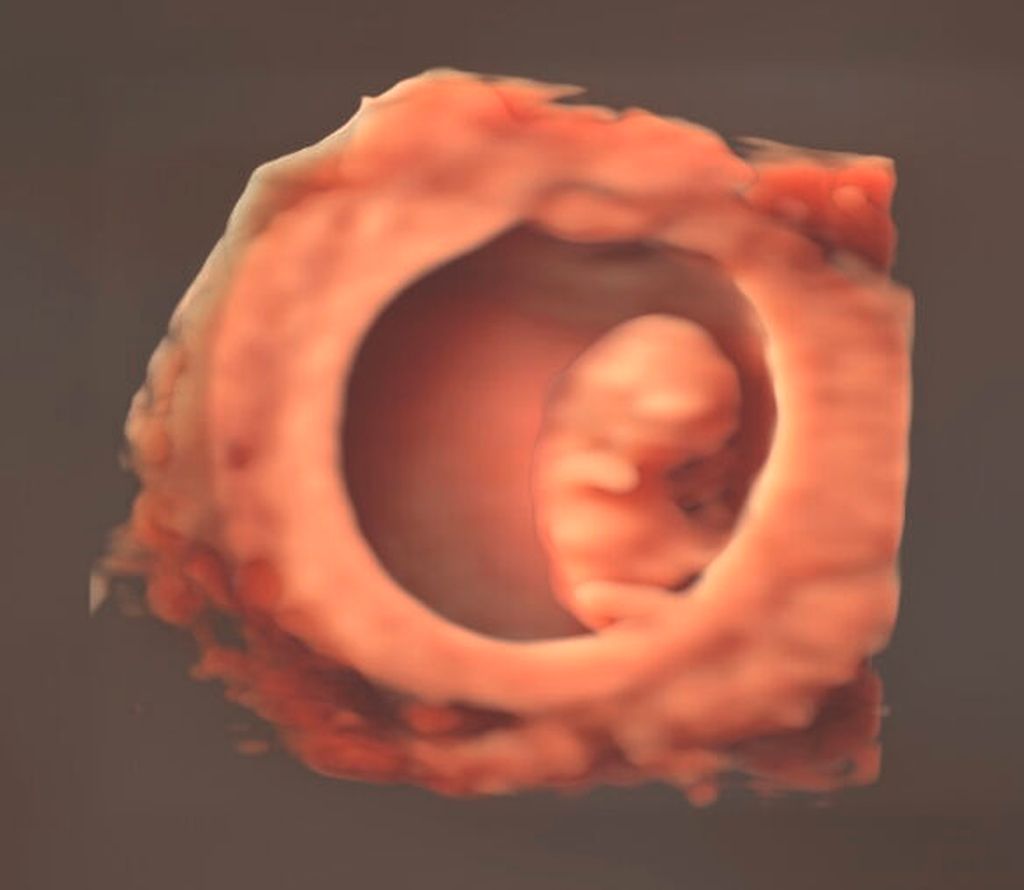

Im Bereich der Perinealsonografie des Beckenbodens ermöglicht das 3D-Verfahren etwa die Visualisierung von Avulsionen des Musculus pubovisceralis. Weitere spannende Einsatzmöglichkeiten bietet das gesamte Spektrum der Frühschwangerschaft, welches je nach Definition ebenfalls der «gynäkologischen» Sonografie zugerechnet werden kann (Abb. 12). Diese Aufzählung erhebt keinen Anspruch auf Vollständigkeit, und wir dürfen auf zukünftige Entwicklungen und Publikationen gespannt sein.